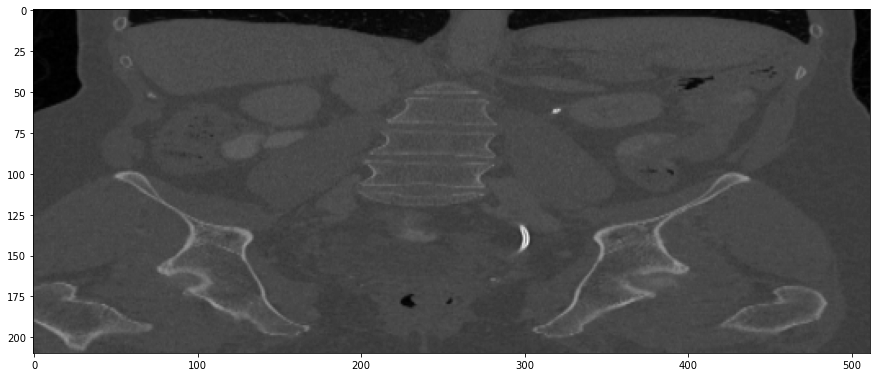

The results from all conducted experiments, represented as mean ±plus-or-minus\pm standard deviation, are tabulated in this section. We assessed the performance of our proposed simulation method against Simple Averaging, Gaussian Averaging, and Direct Downsampling. This was accomplished by simulating images with a thickness of 3mm from those with a thickness of 1mm, utilizing the 2016 Low Dose CT Grand Challenge dataset. The results outlined in Table III provide a comparative analysis of different thick-slice simulation methods used in two datasets from the 2016 Low Dose CT Grand Challenge. Both the PSNR and the RMSE were used as key performance indicators for these methods. The data clearly demonstrate that the proposed method significantly outperformed Simple Averaging, Gaussian Averaging, and Direct Downsampling in both datasets (D45 and B30). The highest PSNR values were obtained with the proposed method, yielding 49.7369 ±plus-or-minus\pm 2.5223 and 48.5801 ±plus-or-minus\pm 7.3271 for D45 and B30 datasets, respectively. The proposed method also registered the lowest RMSE with values of 0.0068 ±plus-or-minus\pm 0.0020 and 0.0108 ±plus-or-minus\pm 0.0099 for D45 and B30, respectively. These results indicate a superior level of accuracy and reliability in the proposed method. The statistically significant differences were confirmed by a Wilcoxon signed-rank test with p-value ¡ 0.05, implying that the improvements from the proposed method were not due to random chance. These findings support our first hypothesis that the proposed simulation method provides a more efficient and precise approach to thick-slice simulations compared to traditional methods. To provide a more comprehensive evaluation, visual comparisons from axial, coronal and sagittal plane were also undertaken, as depicted in Figures 2 to 4. In summary, Our proposed method demonstrated substantial enhancements in terms of both PSNR and RMSE, indicating a distribution more closely aligned with the authentic thick-slice image.

Refer to caption

(a) True Thick-slice image

(b) Simple Averaging

RMSE: 0.0357, PSNR: 34.9781

(c) Gaussian Averaging

RMSE: 0.0454, PSNR: 32.8866

(d) Direct Downsampling

RMSE: 0.0486, PSNR: 32.2861

(e) Proposed Simulation

RMSE: 0.0070, PSNR: 49.1774

Figure 4: Sagittal-plane thick-slice image quality comparison across four simulation methods.